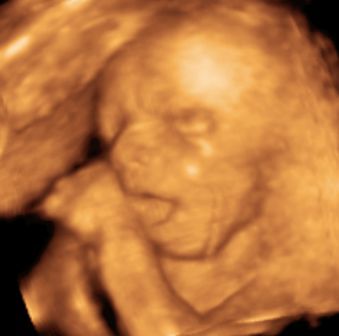

Na, és rakok fel pár képet: Btw: Tiszta apja! :)

Kép Megtalálta az ujját... Kép Cumizik :) Kép Nagyon cumizik :) Bal kezes lesz úgy tűnik. :) Kép Kép Turcsi nózi :)